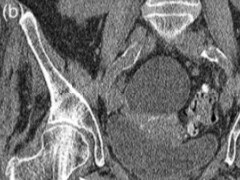

• 狗戴项圈征

狗戴项圈征